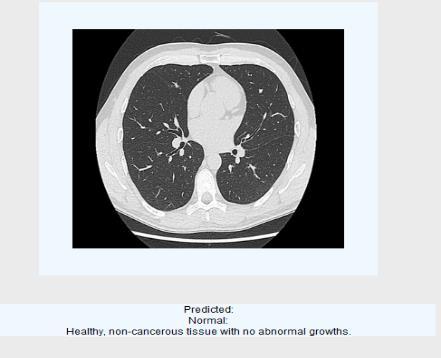

2.3.3Classification output images:

Fig5: Predictedasnormalhealthynon-canceroustissue